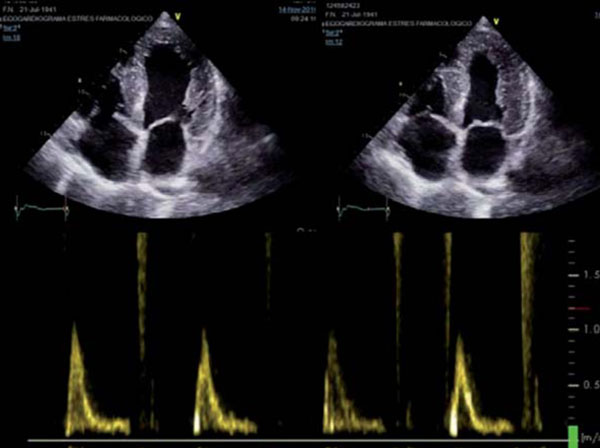

Paciente masculino de 75 años, sin antecedentes de cardiopatía, hipertenso, dislipidémico e hipotiroideo, con cuadro de disnea progresiva. En el ECG se observa ritmo sinusal de 63 cpm, P y PR normales, con bloqueo completo de rama derecha, hemibloqueo anterior izquierdo y alteraciones difusas de repolarización, sin minivoltajes (Figura 1). El eco Doppler mostró severo engrosamiento del VI, hipocontractilidad global más marcada en pared anterior, fracción de eyección del ventrículo izquierdo (FEVI) de 30% y disfunción diastólica severa, configurando un patrón de miocardiopatía hipertrófica (Figura 2). Con este resultado se realiza RM que informa, en secuencia de RT, imposibilidad de anulación del miocardio con diferentes tiempos de inversión, compatible con la presencia de amiloidosis. Presenta además RT del VD, con QALE score de 12 (Figura 3). Dada la disnea aparentemente desproporcionada, se realiza centellograma de perfusión miocárdica con 99mTc-sestamibi con estrés farmacológico para descartar componente isqué mico, que no demuestra alteraciones de la perfusión y FEVI <50% (Figura 4).

Figura 2: Ecocardiograma con enfoque apical de 4 cámaras en sístole (izquierda) y diástole (derecha) mostrando paredes engrosadas de manera concéntrica y simétrica, con aspecto de “vidrio esmerilado”. Patrón Doppler de tipo restrictivo (abajo), con llenado rápido y corto, onda e prominente y onda a de baja velocidad, ausencia de patada y desaceleración rápida.